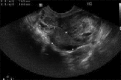

Primary ovarian ectopic pregnancy is a rare entity and is associated with rupture very early in the gestation. We present a case of ovarian pregnancy in a primi gravida, which ruptured relatively late in the first trimester. The patient did not have any predisposing factors for ovarian pregnancy. The case was managed laparoscopically, and the diagnosis was based on surgical and histopathological findings.